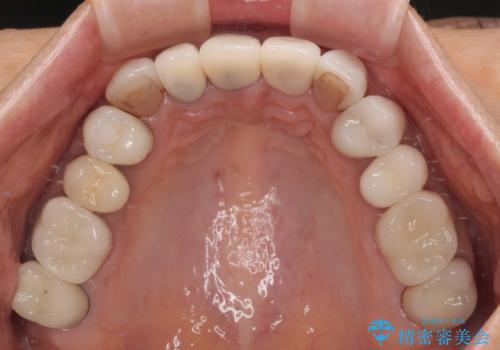

- 前歯のセラミックが欠けたり色調が不揃いであったりすることを気にして来院された患者様です。

20年以上前から、むし歯になったり詰め物が欠けたりする度に部分的に処置を行ってきたそうですが、この際統一感のある前歯にしたいとのことで、上顎前歯9本をオールセラミッククラウンによる補綴治療を行うこととしました。

色調が統一されるだけでなく、歯肉ラインに見えていた茶色の境目も綺麗に改善されました。